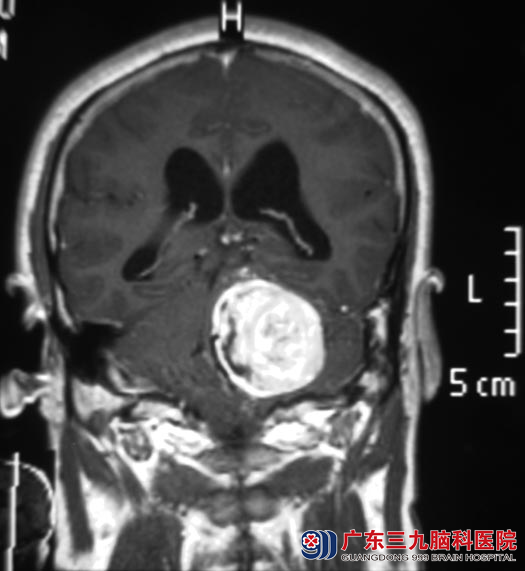

8月23日,温先生蹲下后站起来时突然晕厥摔倒,送当地医院行头颅CT检查,提示:左侧桥小脑角区占位性病变,考虑听神经瘤可能性大。

9月4日,广东三九脑科医院综合神经外科 鲁明主任主刀行“左侧听神经瘤切除术”,因肿瘤位置深入至内听道,经过8个小时的努力,成功将肿瘤全切,完整保留面神经和脑干功能。术后温先生的左耳听力较术前有明显好转,个人反应速度及走路的协调性也明显改善,未出现面瘫等其它症状。